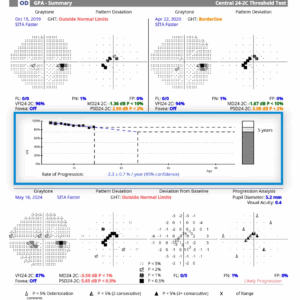

Advancing our capabilities in diagnosing and managing glaucoma and other optic nerve disorders, the ZEISS Humphrey Visual Field Analyser stands as a cornerstone of our diagnostic arsenal. This sophisticated instrument allows us to pinpoint deviations in the peripheral vision with unprecedented accuracy. Understanding the nuances of visual field deficits is crucial, especially in conditions like glaucoma, where peripheral vision can diminish unnoticed until the later stages.

1. Automated and Adaptive Testing

The Humphrey Visual Field Analyser utilises an intuitive algorithm that tailors testing parameters in real time, ensuring that the assessment is both thorough and patient-specific.

2. In-depth Data Analysis:

The system’s robust software analyses a comprehensive array of data points, enabling our specialists to discern even the most subtle changes in a patient’s visual field over time. Consequently, this facilitates early detection and allows for timely intervention.

3. Patient Comfort and Efficiency:

Designed with the patient experience in mind, the analyser provides a comfortable and efficient testing environment, enabling patients to remain focused throughout the process. This optimised experience ensures the collection of high-quality data with minimal strain on the patient.